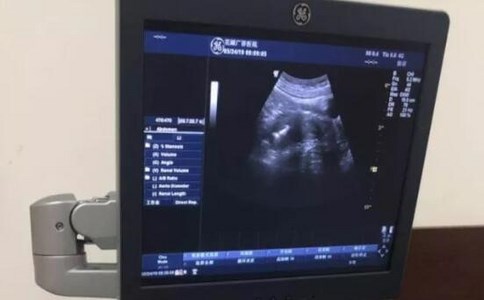

陰道B超,也稱為經(jīng)陰道超聲檢查,是一種醫(yī)學(xué)影像技術(shù),通過高頻超聲探頭進(jìn)入陰道進(jìn)行盆腔器官的檢查。在比較陰道B超和腹部B超哪個安全時,我們需要從多個角度進(jìn)行考慮。以下是對陰道B超的詳細(xì)介紹:

優(yōu)點:圖像清晰度高,受腹部脂肪和腸道氣體干擾小;無需憋尿,檢查過程相對簡便。